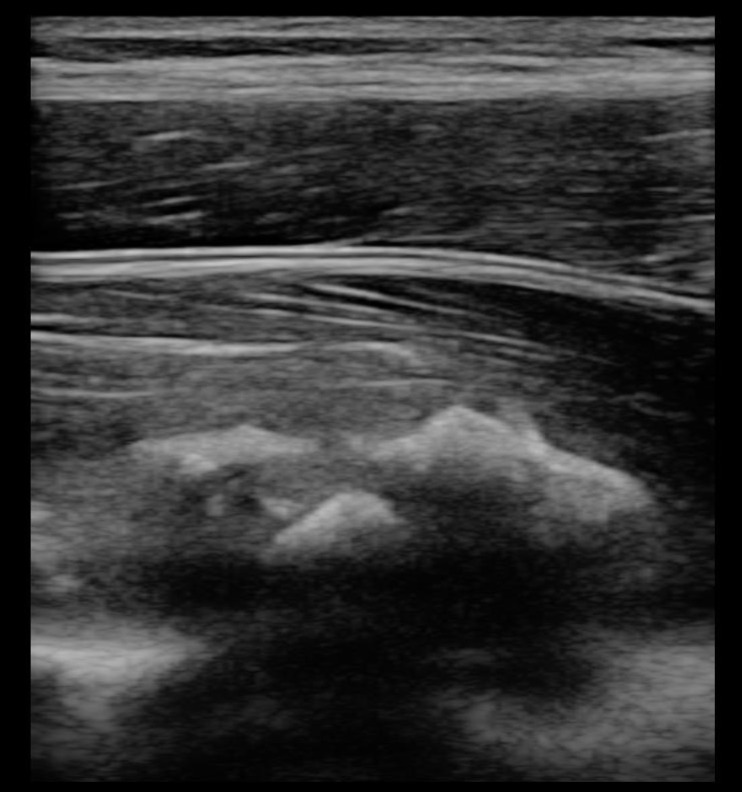

下記エコー画像は他院にて太ももの打撲を適切に処置をしていただけなく、

悪化し骨化性筋炎に移行してしまった症例です。